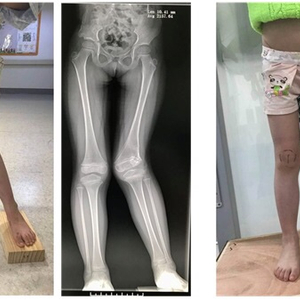

12岁的小龙患有多发内生软骨瘤病,这是一种软骨异常发育,引起肢体短缩和畸形的病症。因全身多处软骨瘤导致双下肢长短相差10厘米。随着年龄的增长畸形复发且越来越严重,家人辗转多家医院后来到上海市儿童医院,在骨科应灏主任领衔下,赵利华副主任医师的四肢畸形矫治团队为小龙进行了畸形矫治手术、安装了目前世界上最先进的环形矫形外固定支架(Taylor三维空间外固定支架),经过85天的畸形矫治后,小龙的右下肢就可以延长10厘米,基本“拉平”双下肢巨大的长短差异。

小龙3岁时,妈妈发现他的右下肢有异常,右侧膝关节和右下肢明显内翻畸形、右下肢比左下肢明显短缩,经过检查后诊断为多发性内生软骨瘤病,在外地初次手术后畸形得到有效矫正,但随着小龙年龄的增长,右下肢畸形复发并明显加重,近10年来,小龙尽管一直在接受不同方案的畸形矫治(包括临时性骨骺阻滞、截骨畸形矫治等),但最终疗效仍不满意,小龙的右下肢较左下肢短了10余厘米、右膝关节明显内翻,这样的畸形严重影响生活质量,走路跛得越来越厉害,还特别容易摔倒。直到今年7月,小龙的爸爸妈妈抱着最后试一试的态度,来到了四肢畸形矫治经验丰富的上海市儿童医院骨科,在骨科应灏主任领衔下,赵利华副主任医师所在的四肢畸形矫治团队接诊了小龙。

赵利华医师的团队接诊后对小龙进行了详细的检查,又结合他的病史,认为Taylor三维空间外固定支架(TSF支架)是非常适合小龙的矫正方法。不同于一般的支架只能进行一个方向的畸形调整,TSF支架可以同时进行三维空间的畸形矫治,做到一次矫治多维畸形,这就使得原本要几次手术才能完成的矫正,只通过一次手术就可以达到治疗目标,大大减少了患儿的痛苦。赵利华医生介绍,TSF支架还具有操作便捷的特点,孩子出院回家后,家长可以根据畸形矫治处方自行调节支架并达到畸形矫治的目的,只需要定期复查恢复情况,有效提高患者的依从性和治疗的精准度。

手术时,术前的畸形测量及方案制定是最为重要的,要找到最准确的畸形顶点作为畸形矫治的旋转点,对医生的专业技能要求极高;术中由于需要精准安装畸形矫治的外固定参考环、医师需要在术中进行不同方位的术中X光片透视,每台TSF安装和矫治手术耗时较长,平均每安装一套TSF外固定架需要2-3小时,小龙的畸形严重,需要按照3套支架才能矫治股骨、胫骨和足踝的畸形,因此手术时长达10-11小时,为了保证支架安装和钢钉植入的准确性,医生需要不时地摄片,像小龙的“一场手术下来要 ‘吃’100多次光”,赵利华说。